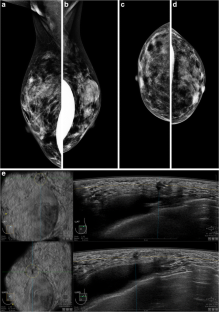

Fig. 1